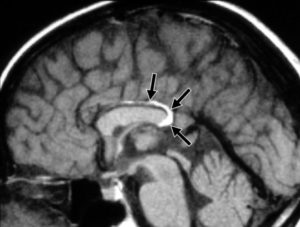

Перикаллезная липома головного мозга на МРТ

Магнитно-резонансная томография или МРТ предоставляет точную информацию о степени развития опухоли.

Диагностирование с помощью данного метода намного результативнее, чем КТ или УЗИ, так как на МРТ есть возможность получить трёхмерное изображение липомы, что является более детальным снимком.

Жировик имеет резко очерченную форму на полученных изображениях. Главный признак обнаружения липомы – высокая интенсивность сигнала жировой ткани при обнаружении патологии.